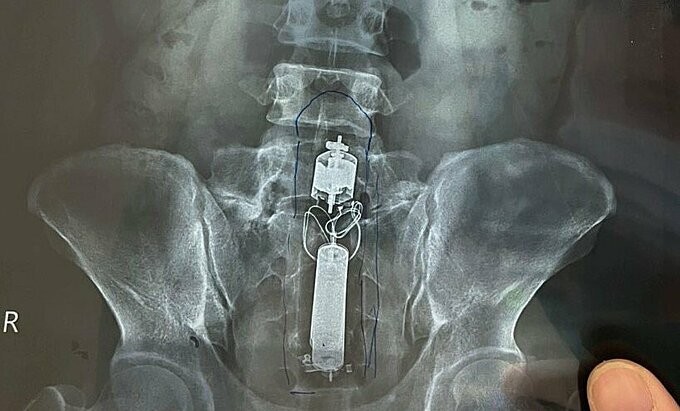

Người đàn ông mắc kẹt dương vật giả trong trực tràng

Đại tá, tiến sĩ Trần Hà Hiếu, Chủ nhiệm Khoa Nội Tiêu hóa, ngày 4/2, cho biết để bệnh nhân tránh được cuộc mổ lớn và phải làm hậu môn nhân tạo, các bác sĩ quyết định nội soi gắp dị vật. Dị vật quá to, hiếm gặp nên không có sẵn dụng cụ chuyên dụng, kẹt ở vị trí khó, các bác sĩ phải cắt đốt polyp để gắp.

au hơn hai giờ nội soi không thành công, bác sĩ Trần Văn Hiều cùng ê kíp quyết định cho bệnh nhân nghỉ, tiến hành thụt tháo. May mắn dị vật trôi dần xuống dưới, bác sĩ tóm được đuôi dụng cụ, kéo ra ngoài.

Theo bác sĩ Hiếu, đây là lần đầu tiếp nhận dị vật kích thước lớn như vậy trong cơ thể bệnh nhân. Nhờ dụng cụ suôn, không góc cạnh, không sắc nhọn nên bác sĩ có thể lấy dị vật qua ngả nội soi.

Bác sĩ khuyến cáo người sử dụng các dụng cụ hỗ trợ tình dục phải cẩn trọng, tránh nguy cơ tổn thương, rách, chảy máu vùng hậu môn trực tràng vì trực tràng rất mỏng. Khi xảy ra sự cố, cần đến bệnh viện để bác sĩ hỗ trợ kịp thời, không tự xử lý, tránh gây các tổn thương lớn hơn.